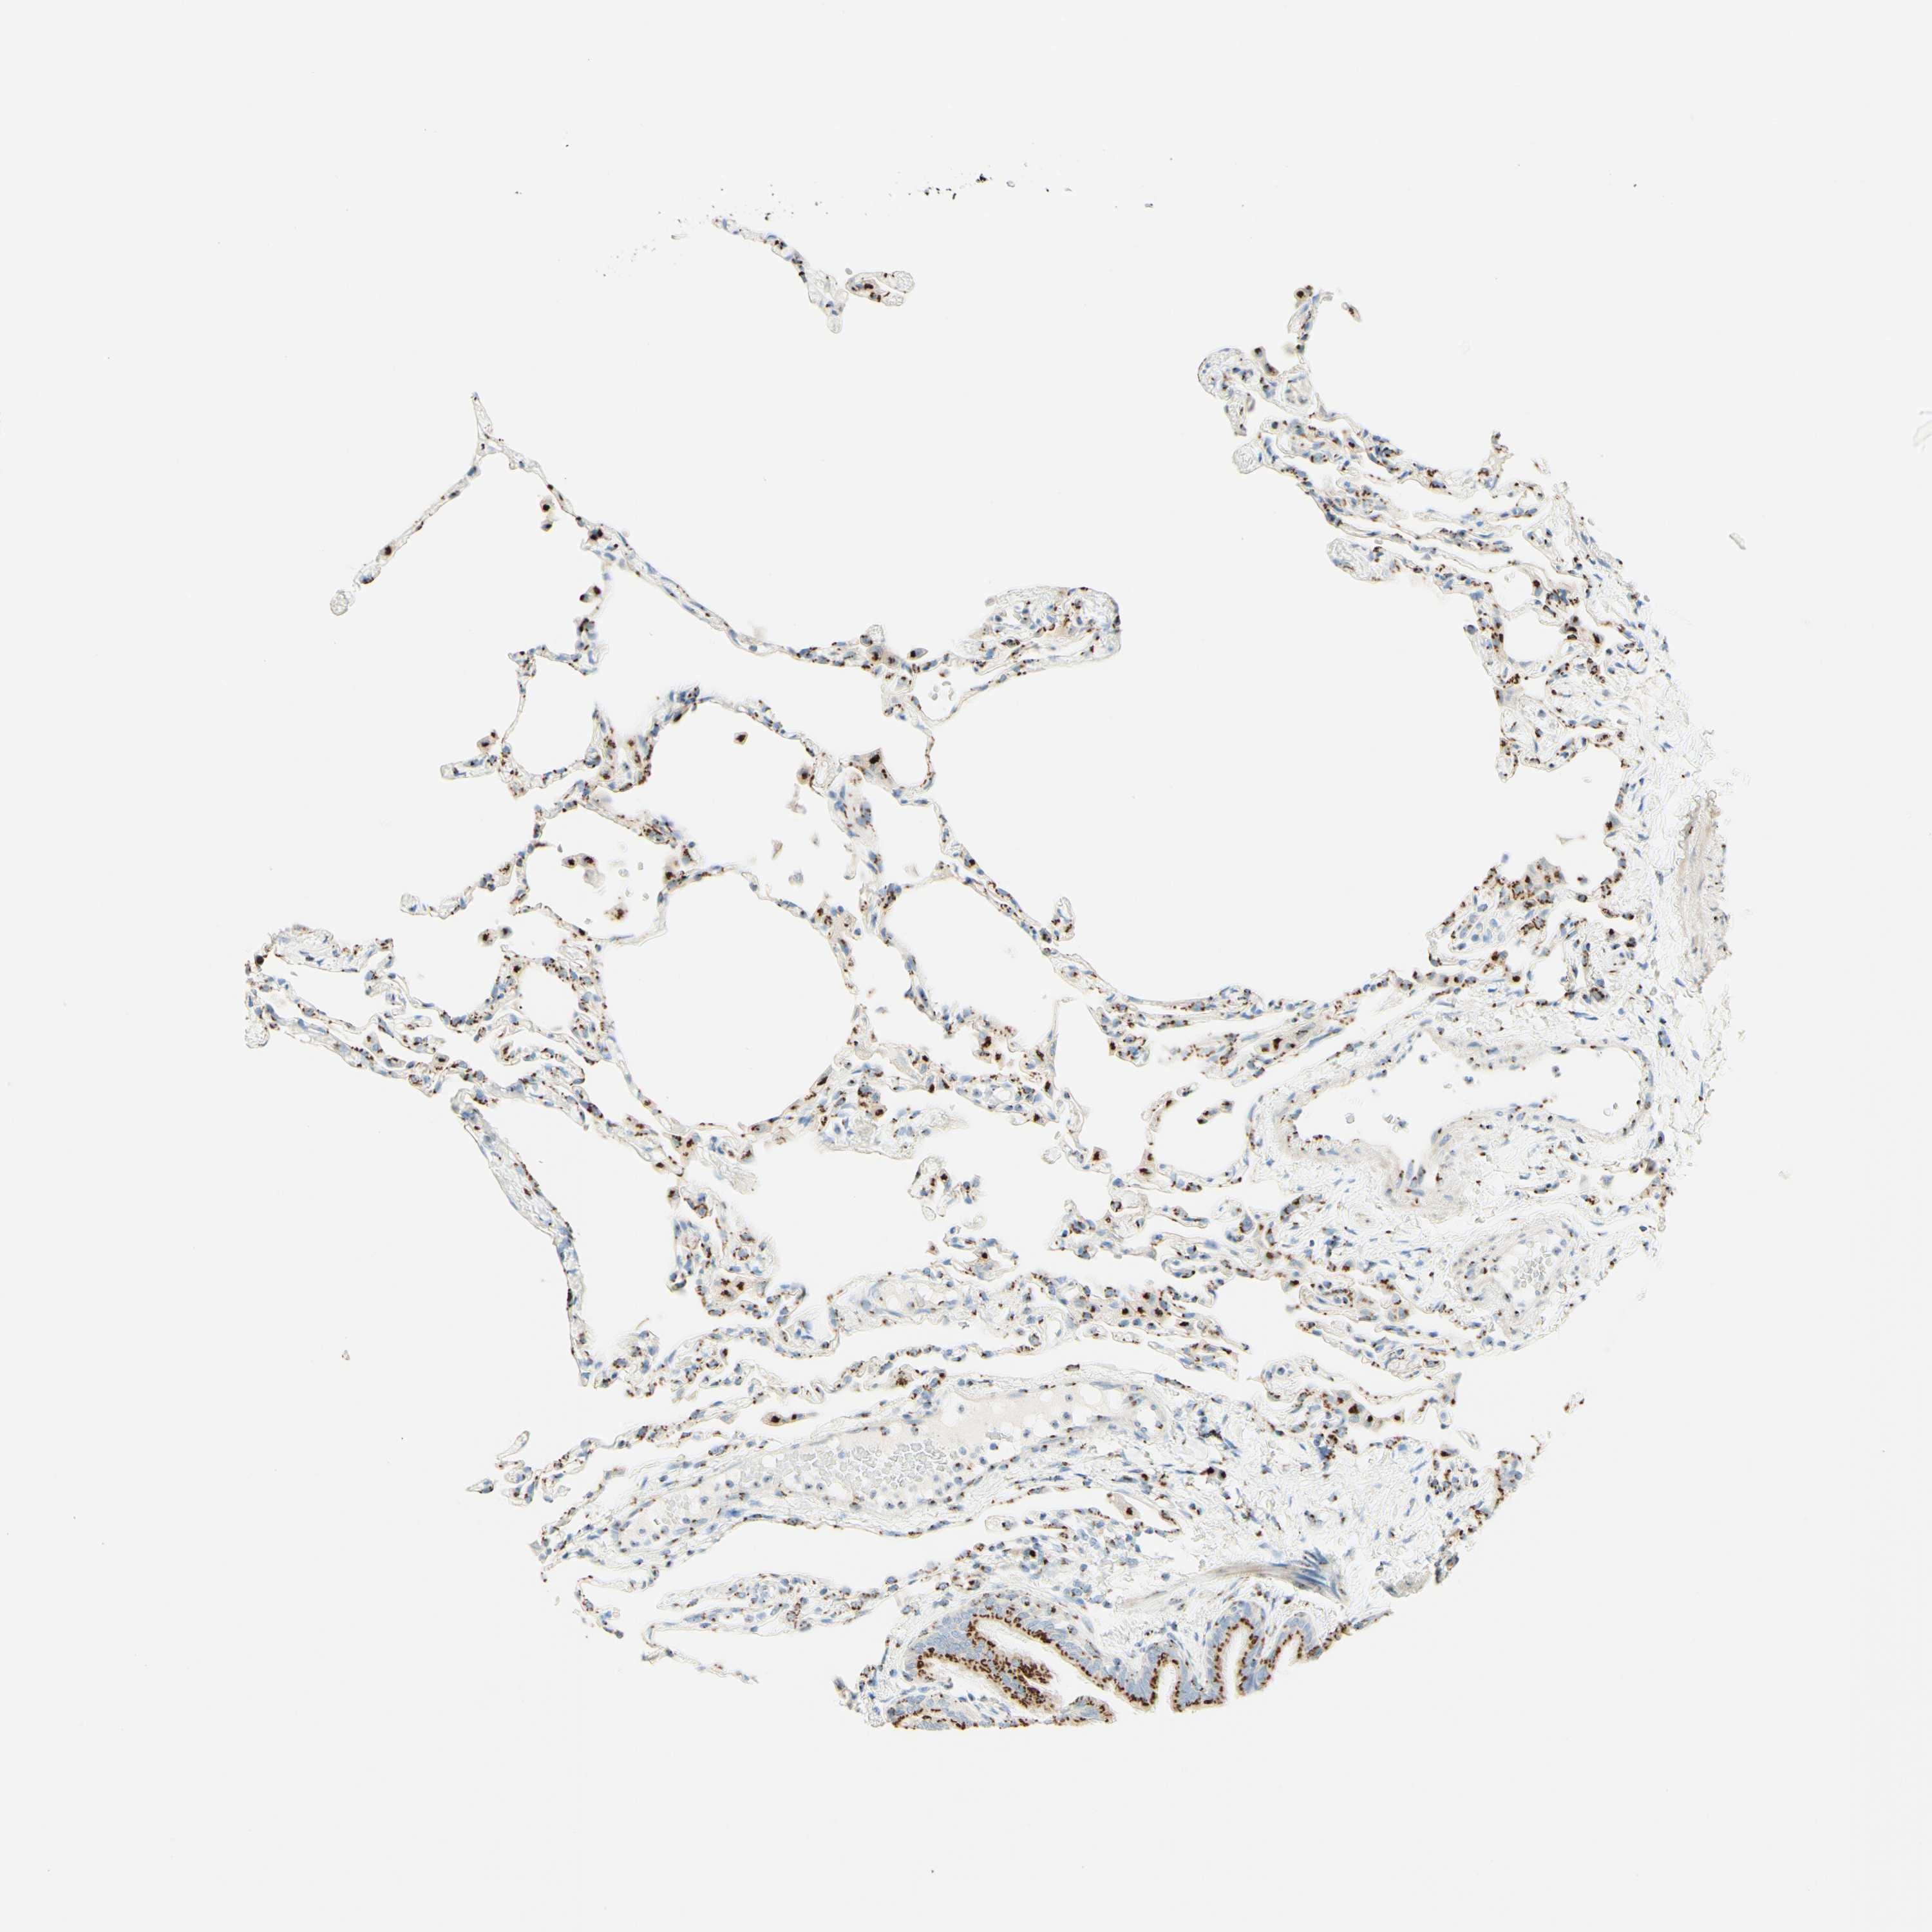

LUNG - Antibody stainingi

Antibody staining in the annotated cell types in the current human tissue is reported as not detected, low, medium, or high, based on conventional immunohistochemistry profiling in selected tissues. This score is based on the combination of the staining intensity and fraction of stained cells.

Each image is clickable and will lead to virtual microscopy that enables deeper exploration of all samples and also displays staining intensity scores, fraction scores and subcellular localization as well as patient and tissue information for each sample.

Antibody HPA011008Antibody HPA011555

Alveolar cells High-

Alveolar cells type I -High

Alveolar cells type II -High

Endothelial cells -Not detected

Macrophages HighHigh